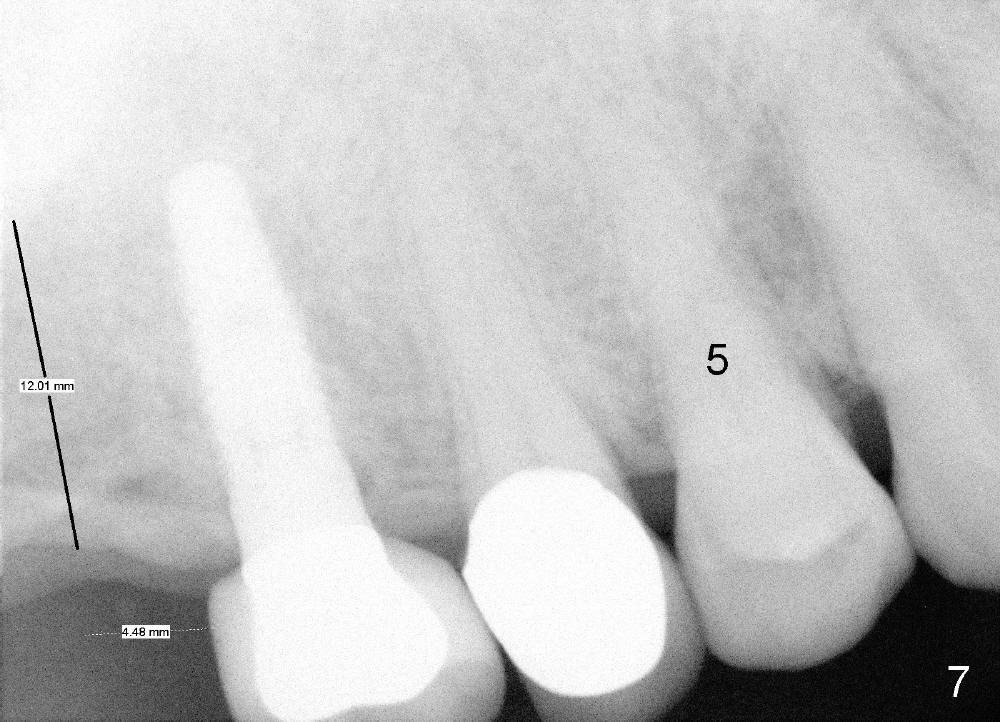

Further search of the patient's files finds X-ray taken prior to #5 extraction (Fig.7). Bone height is estimated 12 mm. Since the mesiodistal width of the 1st molar is less than 10 mm (Fig.8), the center of the osteotomy at the site of #2 should be 4.5 mm (3.5 mm from the 2 mm pilot drill). If the bone allows, 5.3x12 implant will be placed.